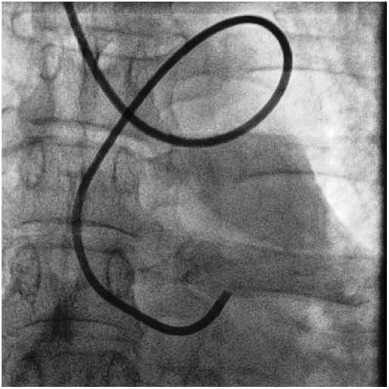

Postamble: A true abnormal course

Though, It might appear prudent to avoid the radial route when encountering anomalous subclavian arteries, the reality is different and adventurous. We have acquired great expertise and successful PTCAs have been done through these tortuous vascular highways.

This is a case report from Dr H.S. Isser, Gunjan Garg, from Safdarjung hospital New Delhi.